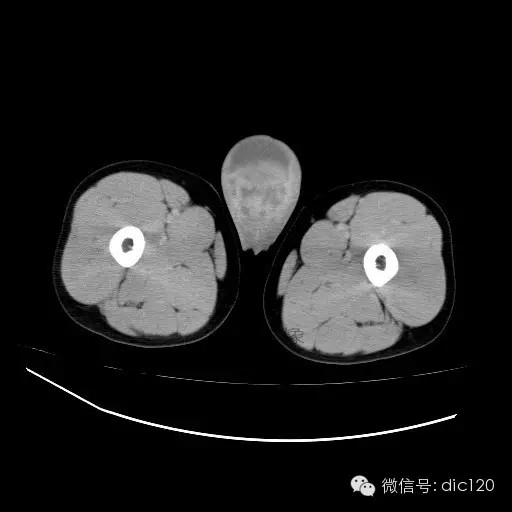

【影像表现】

青年男性,右侧睾丸肿大,边界清晰,增强后睾丸不均匀中度强化,内可见多灶囊变坏死区,动脉期肿块内有细小动脉血管显示,延迟期可见分隔样强化,鞘膜囊可见积液。

定位定性:右侧睾丸恶性肿瘤。

【影像诊断】

右侧睾丸精原细胞瘤,右侧睾丸鞘膜积液。